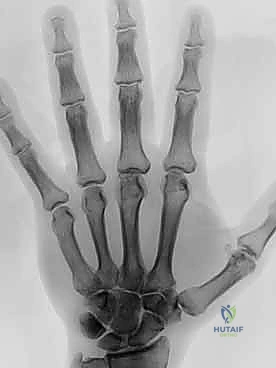

5. اختبار الاستقرار والحركة (Intraoperative Testing)

قبل إغلاق الجرح، يقوم الدكتور هطيف بثني وفرد الإصبع للتأكد من أن المفصل الجديد يتحرك بسلاسة، وأن اصطفاف الأصابع قد عاد إلى وضعه التشريحي الطبيعي، وأن التشوه قد تم تصحيحه بالكامل.

6. إصلاح الأنسجة الرخوة والإغلاق

- الأسبوع الأول إلى الثاني: يتم وضع اليد في جبيرة ديناميكية مخصصة. هذه الجبيرة تدعم اليد في وضع مستقيم وتمنع الانحراف، لكنها تسمح بحركة محسوبة للأصابع (بمساعدة أشرطة مطاطية) لمنع التيبس.

عانت السيدة مريم من التهاب المفاصل الروماتويدي لسنوات طويلة، مما أدى إلى انحراف شديد في أصابع يدها اليمنى وألم يمنعها من إعداد الطعام لأسرتها. بعد زيارتها لعيادة الأستاذ الدكتور محمد هطيف في صنعاء، تم التخطيط لإجراء استبدال لأربعة مفاصل (MCP) بالسيليكون في عملية واحدة. اليوم، وبعد 6 أشهر من الجراحة والتأهيل، عادت يد مريم مستقيمة، اختفى الألم تماماً، وعادت لتمارس هوايتها في الخياطة والطبخ بابتسامة لم تفارق وجهها.